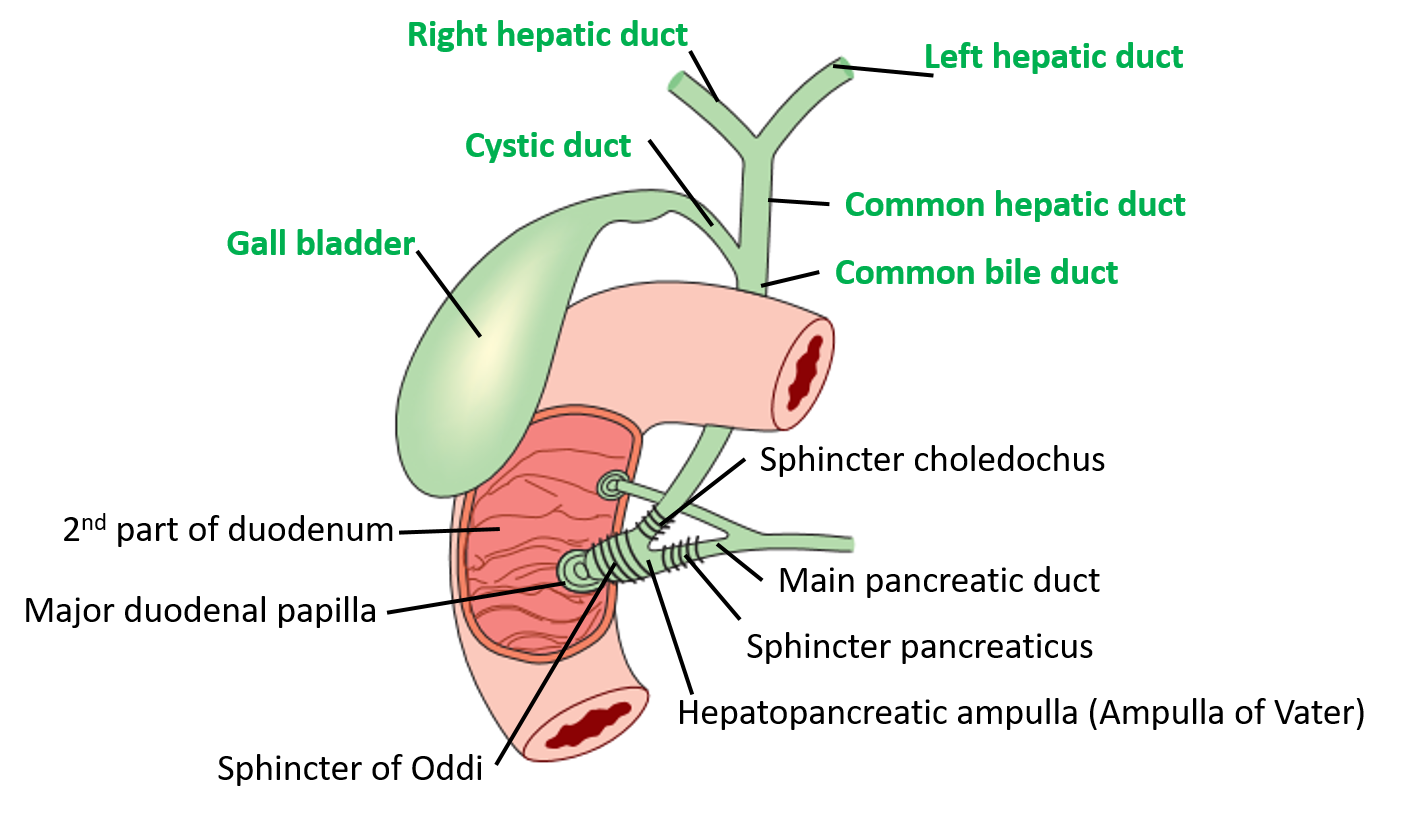

Bij een galwegontsteking (cholangitis) zijn de galwegen in of buiten de lever ontstoken. In de lever zitten veel kleine galkanaaltjes. Deze komen samen in de grotere galwegen. Via de grotere galwegen wordt de galvloeistof afgevoerd naar de galblaas en vervolgens naar de dunne darm. De galblaas.. Auszug. Die extra hepatischen Gallen wege in Form des Gallengangs und der Gallenblase garantieren den großen täglichen Bedarf an fettemulgierender Galle. Jede Unwegsamkeit darin provoziert ein Stenosemuster mit entsprechendem Gallenrückstau, der akut zum tödlichen Leberversagen und chronisch zu einem fibrodestruktiven Reaktionsmuster und.

De galblaas. Anatomie van de galblaas en galwegen. Anatomie van de twaalfvingerige darm en de

Anatomy of the gallbladder and bile ducts Surgery Oxford International Edition

Lever (Hepar)Galwegen en Galblaas